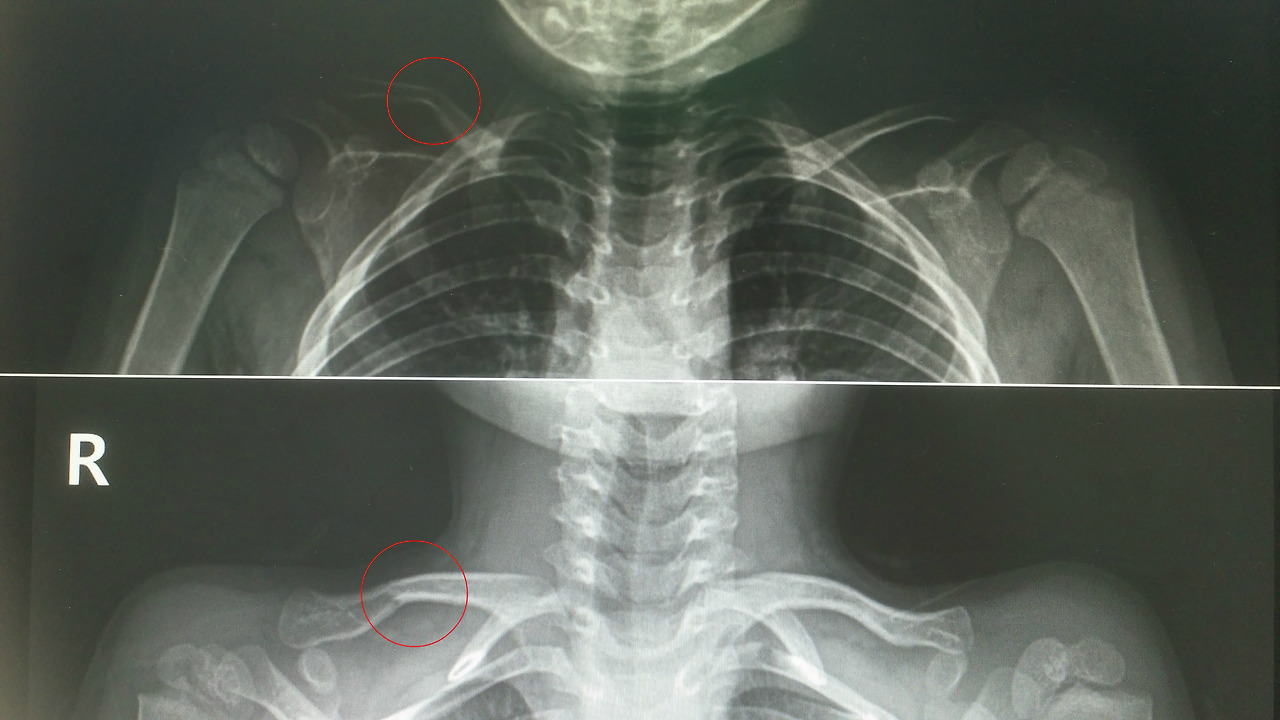

그럼 나머지는 골절이 있는 경우가 남았네요. 놀이터에서 놀다 어깨로 떨어졌거나 제 어렸을 때 이야기처럼 친구 체중에 어깨를 눌린 경우에는 빗장뼈 골절이 흔합니다. 골절 모양에 따라 수술적 치료가 필요한 경우도 있지만 소아의 빗장뼈 골절은 대체로 4주가량 어깨를 뒤로 당겨놓는 것만으로도 잘 치료가 됩니다. 간혹 처음에는 골절선이 보이지 않다가 나중에 확인되거나 아주 약간 각도만 변하는 경우도 있는데 이는 소아 골절의 특징 중 하나입니다. 젖은 나뭇가지가 부러지듯 골절선이 명확하지 않은 경우가 흔하거든요.

또 자주 보이는 골절로 위팔뼈 하단에 생기는 상과 골절(위관절융기 골절)이란 게 있습니다. 팔꿈치로 바닥에 부딪히거나 떨어졌을 때 발생하는데 이 골절도 방사선 검사 결과나 신경학적 이상 유무에 따라 수술 여부를 결정해야 합니다. 많이 어긋나지 않고 신경증상도 없으면 부목을 대고 관찰하게 되지요.